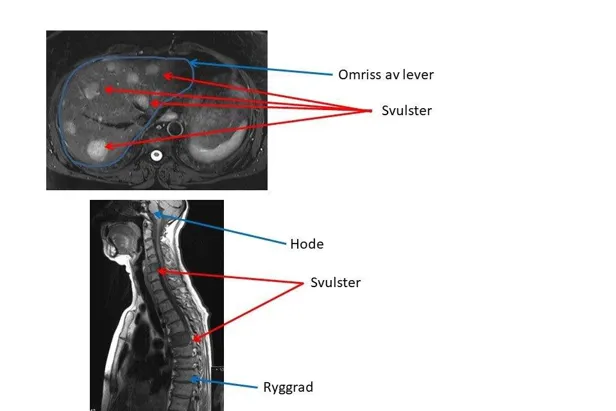

Likeledes vil MR-oppdage flere svulster og gi bedre tolkningsmuligheter av sykelige forandringer ved bruk av kontrast. MR er bedre til å påvise svulster i skjelettet enn CT.